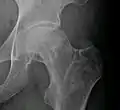

| دراثر نرسیدن خون به سر استخوان ران، قسمتی از غضروف جدا شده است (نمونه درحین عمل تعویض مفصل) | |

در بیماری بافتمردگی بیخونی یا سیاه شدن سر استخوان ران به عللی که دقیقاً مشخص نیست عملکرد رگهایی که خون را به سر استخوان ران میرسانند دچار اشکال شده و خون به اندازه کافی به سر استخوان ران نمیرسد. شکستگی گردن استخوان ران (مثلاً به دلیل تروما) نیز میتواند موجب بروز این مشکل شود. بدنبال کاهش یا قطع خونرسانی به سر استخوان ران، سلولهای آن میمیرند. مرگ سلولها موجب میشود بعد از مدتی استخوان سفتی و قوام خود را از دست داده و نرم شود.

سر استخوان ران در مفصل ران تحت فشار نیروهای بسیار قوی قرار دارد که عمدتاً بر اثر وزن بالا تنه به آن وارد میشود. سر استخوان ران در حالت عادی به راحتی این نیروها را تحمل میکند ولی وقتی استخوان ضعیف و نرم شده باشد نمیتواند این فشارها را تحمل کند. این نیروها و فشارها بتدریج موجب تغییر شکل سر استخوان ران میشوند. سطح بالایی سر استخوان که بیشترین نیروها به آن وارد میشود بتدریج صاف و تخت شده و حالت گرد و کروی خود را از دست میدهد.

در روند بافتمردگی (نکروز) و مردن سر استخوان ران معمولاً غضروفی که سر استخوان ران را پوشانیده هم بدون حمایت استخوان زیرین بتدریج از بین میرود و این تخریب غضروفی روند ساییدگی را شدت میدهد.